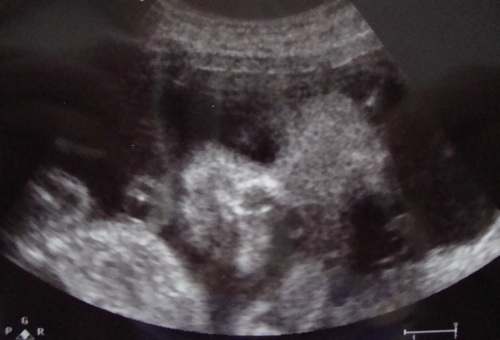

Hát még találékonynak kell lennem, ami bénázgatok itt fekvés közben, az már nagyon komikus, mert persze minden folyton leesik, kiesik, ottmarad, aztán a másik meg, hogy csak a bal oldalamon fekhetek, mert a jobb oldalon van a vesetágulat, azt mondták, ne feküdjek arra, mert az nyomja a vesét, háton nem jó és nem is ajánlott, marad a bal oldal, de így meg már szétzsibbad mindenem

Apa már csak röhögött rajtam, annyira szánalmaska vagyok. De babuka jól van, sokat mozog, én meg szuggerálom a méhszájat, elképzelem, ahogy egy szép nagy szalaggal átkötve jó szorosan bezárom és megfenyegetem, hogy maradjon így.